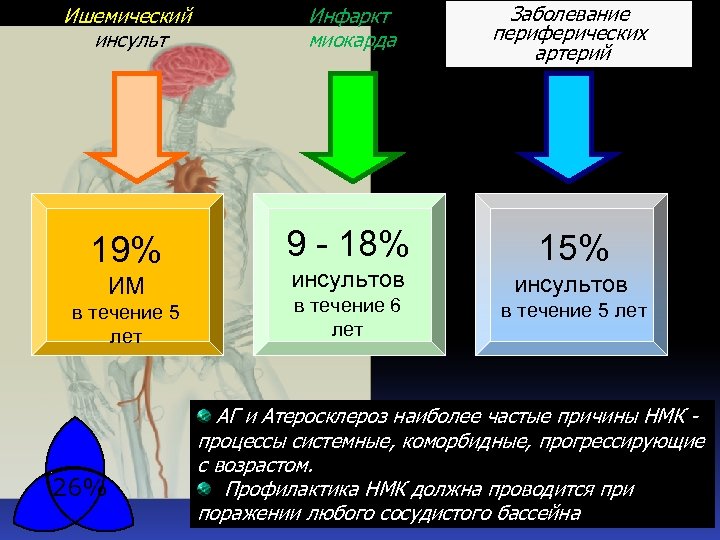

Ишемический инсульт Инфаркт миокарда Заболевание периферических артерий 19% 9 - 18% 15% ИМ в течение 5 лет 26% инсультов в течение 6 лет инсультов в течение 5 лет АГ и Атеросклероз наиболее частые причины НМК процессы системные, коморбидные, прогрессирующие с возрастом. Профилактика НМК должна проводится при поражении любого сосудистого бассейна

Ишемический инсульт Инфаркт миокарда Заболевание периферических артерий 19% 9 - 18% 15% ИМ в течение 5 лет 26% инсультов в течение 6 лет инсультов в течение 5 лет АГ и Атеросклероз наиболее частые причины НМК процессы системные, коморбидные, прогрессирующие с возрастом. Профилактика НМК должна проводится при поражении любого сосудистого бассейна